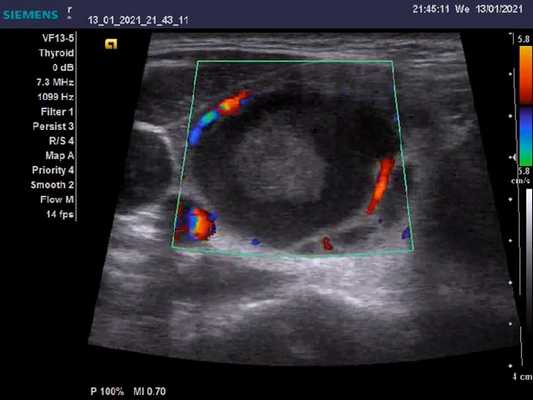

Цветовые и энергетйические допплеровские исследования демонстрируют поразительную гиперваскулярность. Поток в питающих артериях быстрый, более 100 см/с; снижение до менее 40 см/с при лечении интерпретируется как признак хорошего прогноза. Очаговые поражения (узлы) в щитовидной железе с плохим эхо-сигналом при болезни Грейвса-Базеда не зависят от основного заболевания и должны рассматриваться отдельно.

- На УЗИ с ЦДК отмечается увеличение кровотока в паренхиматозной сосудистой системе (турбулентный кровоток с артериовенозными шунтами): «ад щитовидной железы»

- Повышение васкуляризации не коррелирует с функцией щитовидной железы, но отражает воспалительную активность

- Спектральный допплер: увеличение пиковой скорости кровотока (≤ 120 см / сек), в измеренной нижней щитовидной артерии

- Повышенная васкуляризация имеет тенденцию к уменьшению в ответ на лечение

- Повышение васкуляризации наблюдается у пациентов с рецидивом

УЗИ с цветным допплером. Усиление кровотока в паренхиматозной сосудистой системе (турбулентное течение с артериовенозными шунтами): «Ад щитовидной железы». Такое повышение васкуляризация не коррелирует с функцией щитовидной железы, но отражает воспалительную активность. Спектральный допплер: Увеличение пиковой скорости кровотока (≤ 120 см / сек) в измеренной нижней щитовидной артерии. Увеличение сосудистого рисунка имеет тенденцию к уменьшению в ответ на лечение. Обратная картина наблюдается у пациентов с рецидивом.